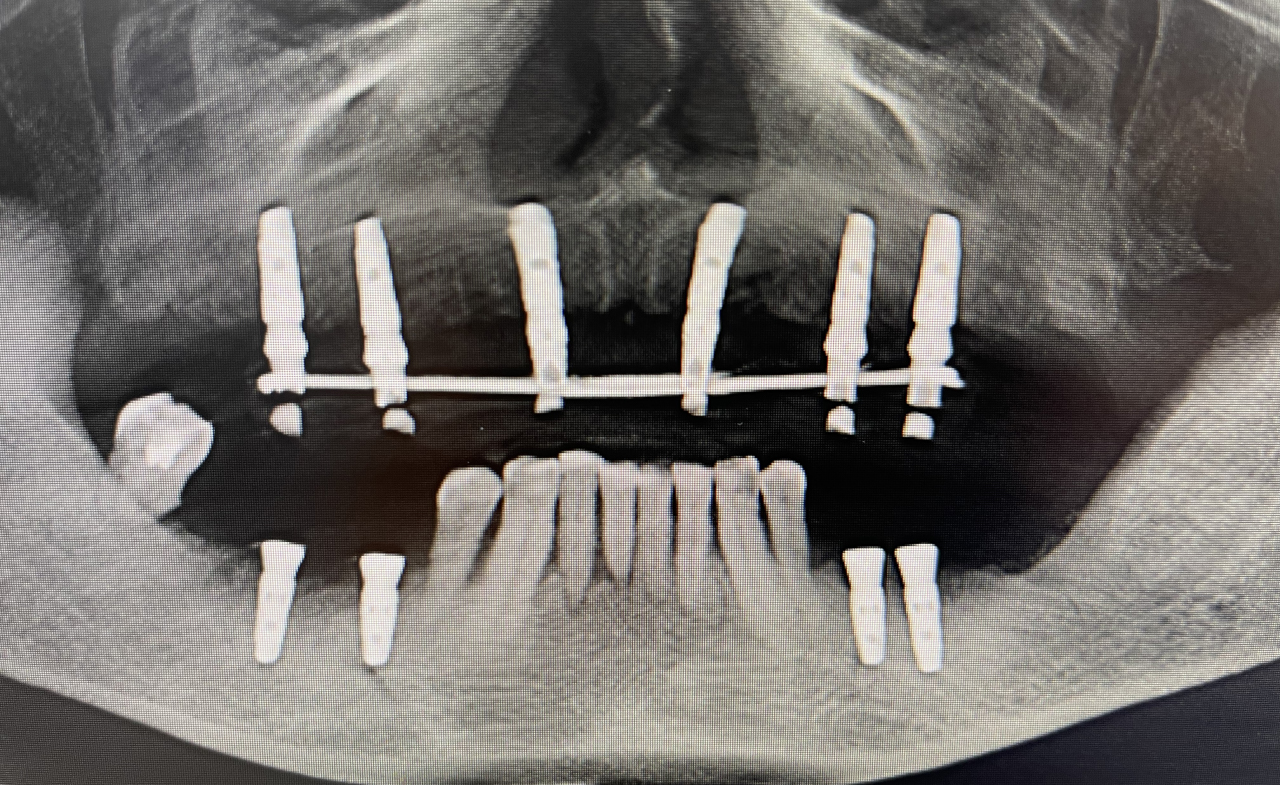

导板引导下种植手术:

上颌植入6颗中科安齿种植体

通过全程数字化导板引导精准植入6颗中科安齿种植体,并且获得非常好的初期稳定性,实现术后即刻修复,患者满意度极佳。